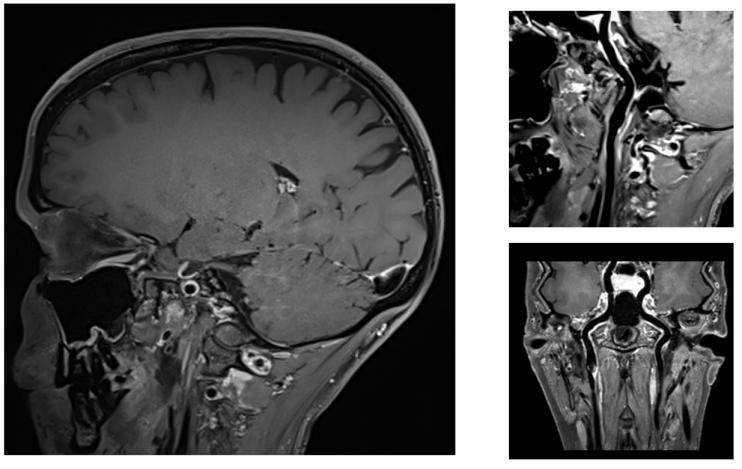

神经系统-血管壁成像

神经系统-全脊柱成像,臂丛神经成像

颈椎成像,使用CoilShim后,压脂不均匀区域的压脂效果明显改善。